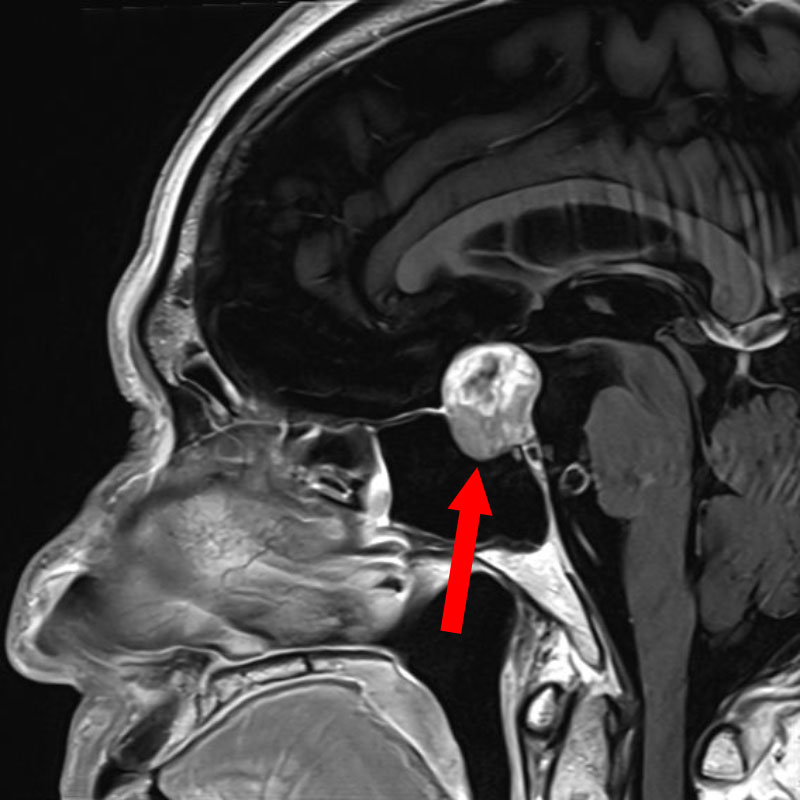

手術前1

手術前2